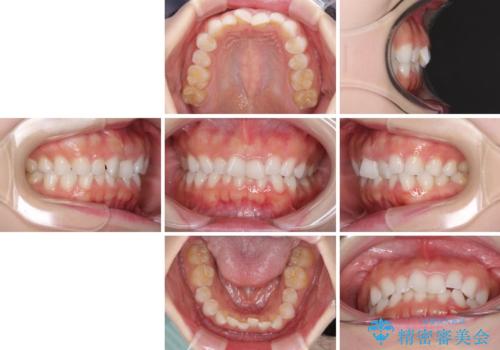

デコボコと深い咬み合わせの改善 インビザラインによる矯正治療

- 口元のデコボコと深い咬み合わせ(ディープバイト)を気にして来院された患者様です。

インビザラインによる上下歯列の拡大と、IPR(歯と歯の間を削る)にるスペースの獲得により、口元のデコボコとディープバイトを改善することとしました。

インビザラインは、装着していない時間がどれだけ短いかが、治療期間を大きく左右します。こちらの患者様は1日22時間以上、毎日欠かさず装着してくださったため、1年強という短期間で満足のいく歯列に整えることができました。